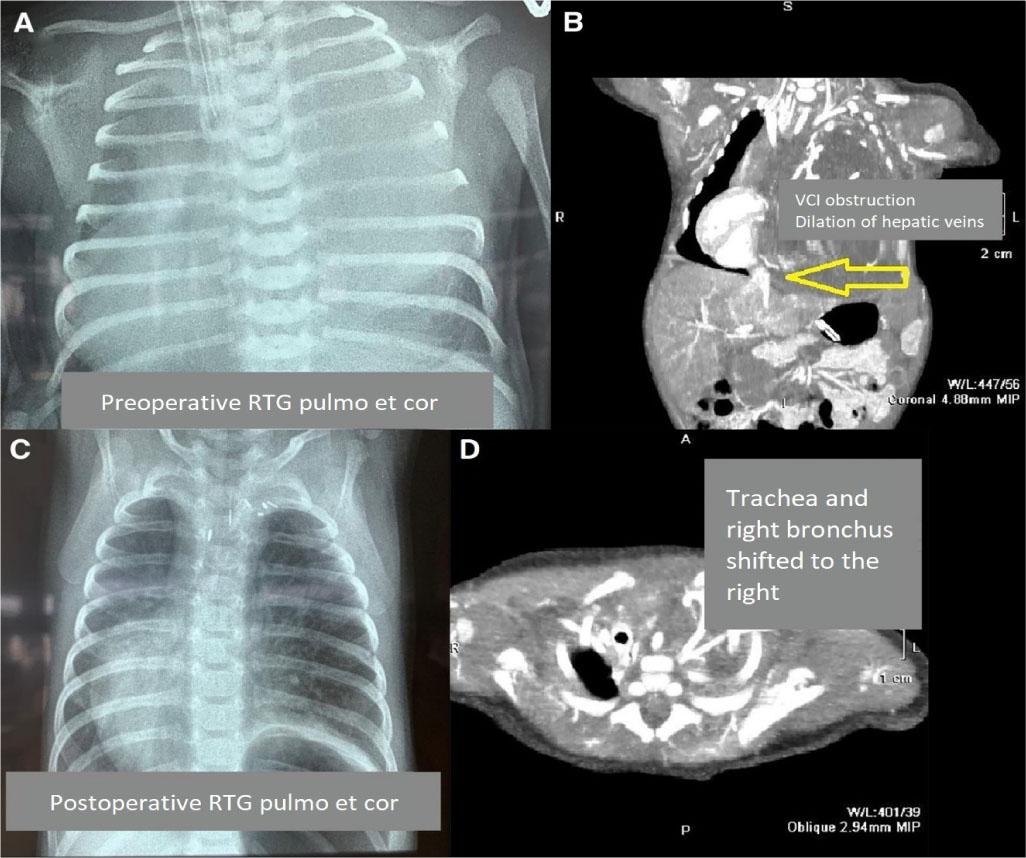

Figure 1: